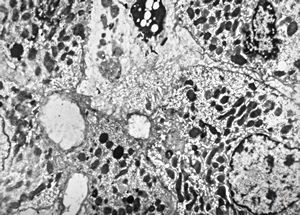

M,66y. | siderosomes

M,66y. | hemosiderin - siderosomes